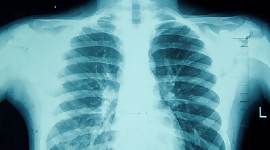

Онкологията, минимално инвазивната хирургия и ортопедията бяха сред най-търсените специалности Българските пациенти все по-често се обръщат към Wiener Privatklinik (WPK) за лечение на сложни заболявания. С над 300 специалисти - 28 от които са включени в Топ 2% на най-цитираните учени в света - WPK предоставя медицински услуги от най-високо ниво в повече от 30 специалности чрез своите 10 специализирани центъра за компетентност. За да отговори на нарастващото търсене от страна на чуждестранните пациенти, WPK стартира мащабен проект за разширяване на стойност 55 милиона евро, който ще удвои капацитета на болницата. Тези инвестиции включват и най-съвременни диагностични технологии. Wiener Privatklinik (WPK), една от най-големите частни болници в Австрия, която за пета поредна година е включена в списъка на най-добрите болници в света, регистрира 67% увеличение на приетите български пациенти през първата половина на 2025 г. Най-търсените медицински услуги са били онкологията, минимално инвазивната хирургия и ортопедията - области, в които WPK се отличава с напреднал експертен опит, най-съвременни технологии и индивидуален подход към грижите. През първата половина на 2025 г. онкологичните заболявания са основната причина българите да се обръщат към WPK. Близо 60% от българските пациенти са лекувани в онкологичния център на WPK Central European Academy, най-комплексния частен онкологичен център в Централна и Източна Европа